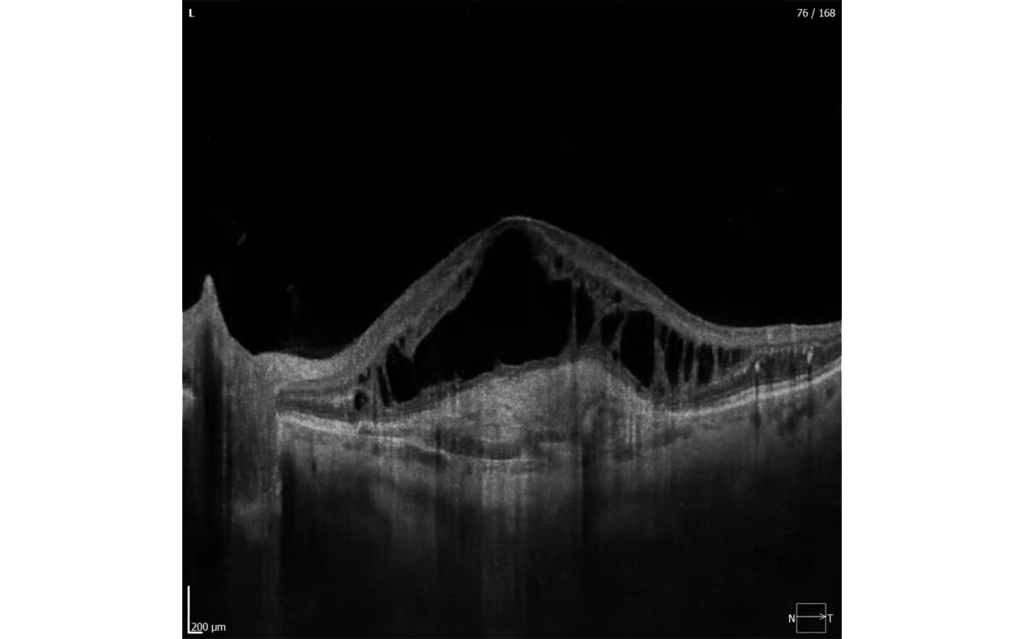

The cataract mode in the REVO series opens up new possibilities for patients with challening cases.

This featureprovides visualisation of structures hidden beneath opaque layers, making it ideal for diagnosing eye conditions thatwere previously difficult or impossible to study in patients with cataract, corneal oedemas or very dense floaters.The cataract mode allows the scanning speed and sensitivity of the OCT to be modified for better visualisation ofpatients with opaque media.